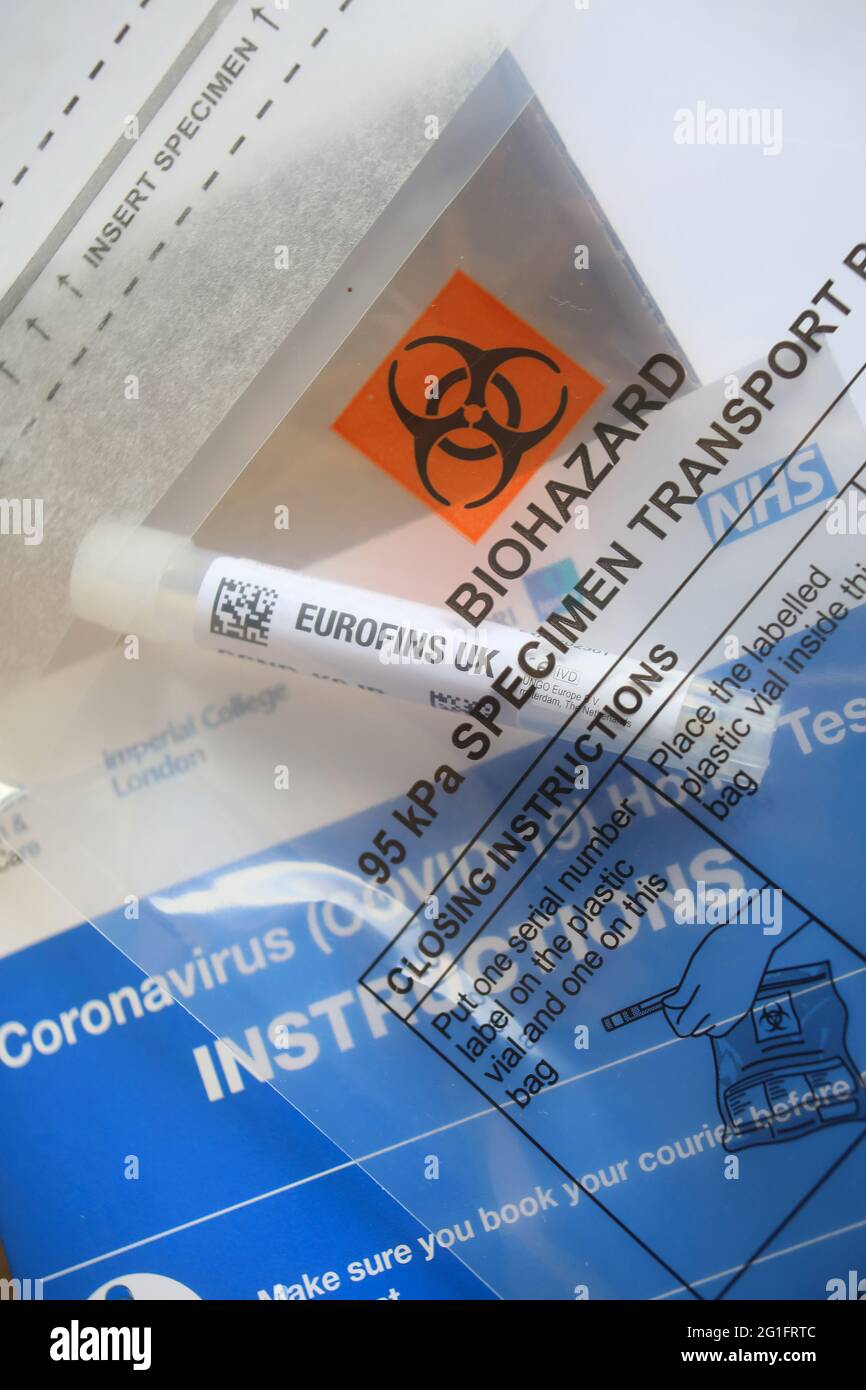

PCR at home test, UK Stock Photohttps://www.alamy.com/image-license-details/?v=1https://www.alamy.com/pcr-at-home-test-uk-image431221852.html

PCR at home test, UK Stock Photohttps://www.alamy.com/image-license-details/?v=1https://www.alamy.com/pcr-at-home-test-uk-image431221852.htmlRM2G1FRTC–PCR at home test, UK